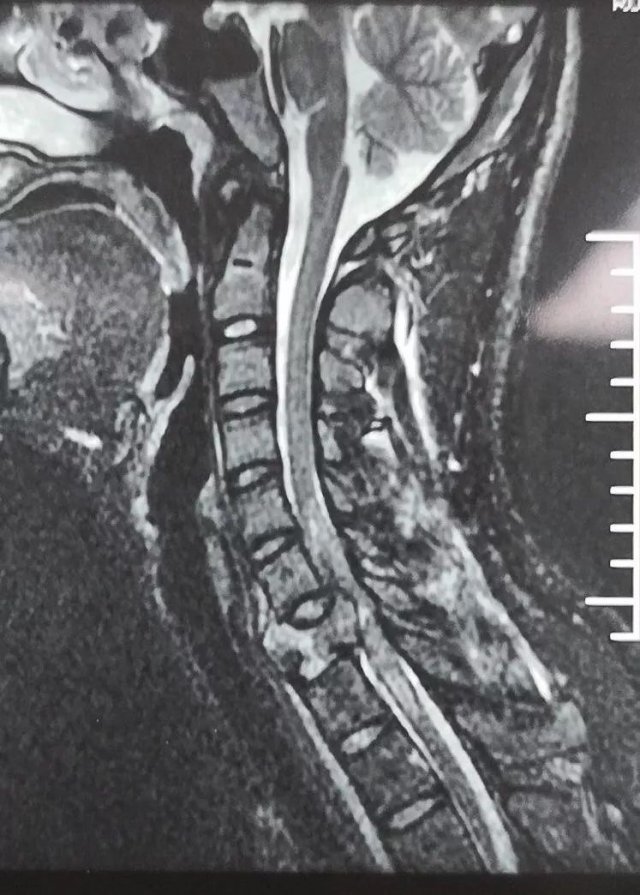

颈椎管狭窄

颈椎椎管狭窄

颈椎椎管狭窄各种原因所致颈椎管狭窄呈现临床症状者称之为颈椎椎管狭窄症。随颈脊髓受压程度而临床症状有所

颈椎管狭窄的概念因此颈椎管狭窄症,是引起椎管狭窄脊髓压迫的各种疾病的统称,不是单一特定的疾病。

椎管狭窄 一般分为:先天发育性(原发性)和后天继发性椎管颈椎由于发育因素,各颈椎的椎管容积较正常狭窄。